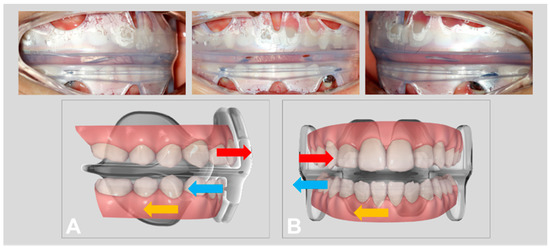

2.5. Treatment Sequence